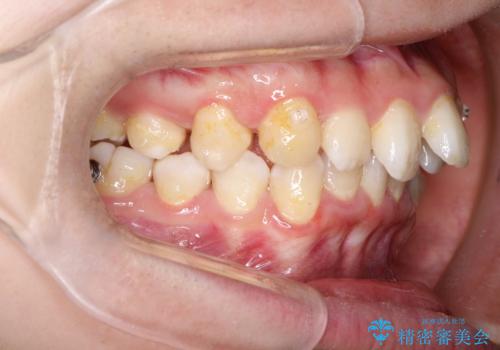

重度のガタガタのインビザラインによる非抜歯矯正

- 全体的なガタガタを気にされて来院されました。

抜歯矯正も考えられる状態でしたが、ご本人的になるべく歯を抜かない矯正を希望されました。

奥歯を後方に移動させるのと、歯と歯の間にわずかに隙間を作ることでスペースを確保して、抜歯をせず歯を並べる計画としました。

ガタガタの度合いが大きかったので少し時間がかかりましたが、非常に協力的な患者様でしたので、抜歯をせず計画通りに治療を終えることができました。